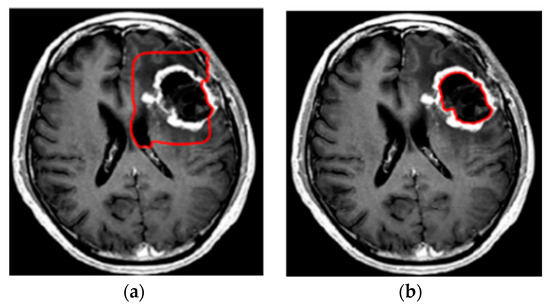

- Khalil, H.; Darwish, S.; Ibrahim, Y.; Hassan, O. 3D-MRI brain tumor detection model using modified version of level set segmentation based on dragonfly algorithm. Symmetry 2020, 12, 1256. [Google Scholar] [CrossRef]